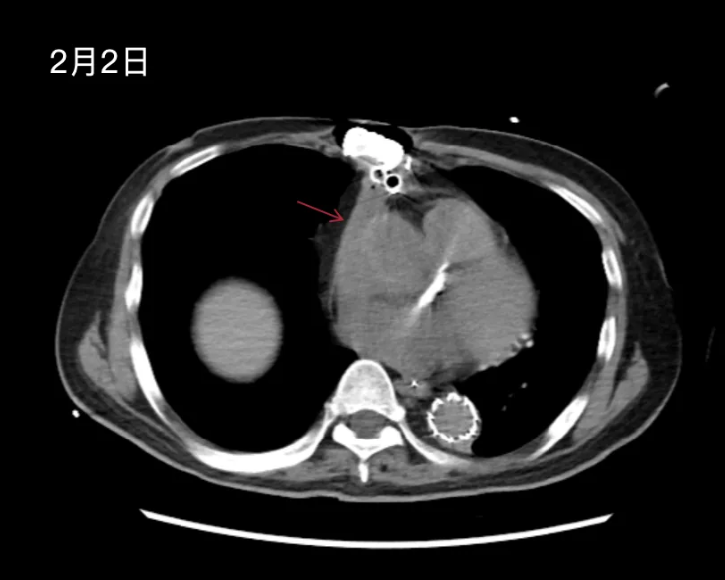

经1个半月充分抗感染治疗,患者仍反复发热(Tmax 37.6-38℃),PCT低水平波动(0.5-1.5ng/ml),复查胸CT(2-02)提示:双肺炎症较前部分吸收,左侧少量胸腔积液,较前减少;纵隔渗出性改变,纵隔引流管置入状态;纵隔多发小淋巴结显影;心脏饱满,主动脉弓术后改变,主动脉根部高密度影,较前变化不大,升主动脉管壁新月形低密度影,较前大致相仿(图4)。心脏彩超(2-03):主动脉机械瓣+孙氏手术术后,主动脉瓣位人工机械瓣功能尚可,机械瓣少量返流,人工血管血流通畅,左室肥厚。

图4.纵隔内可能是感染灶吗?